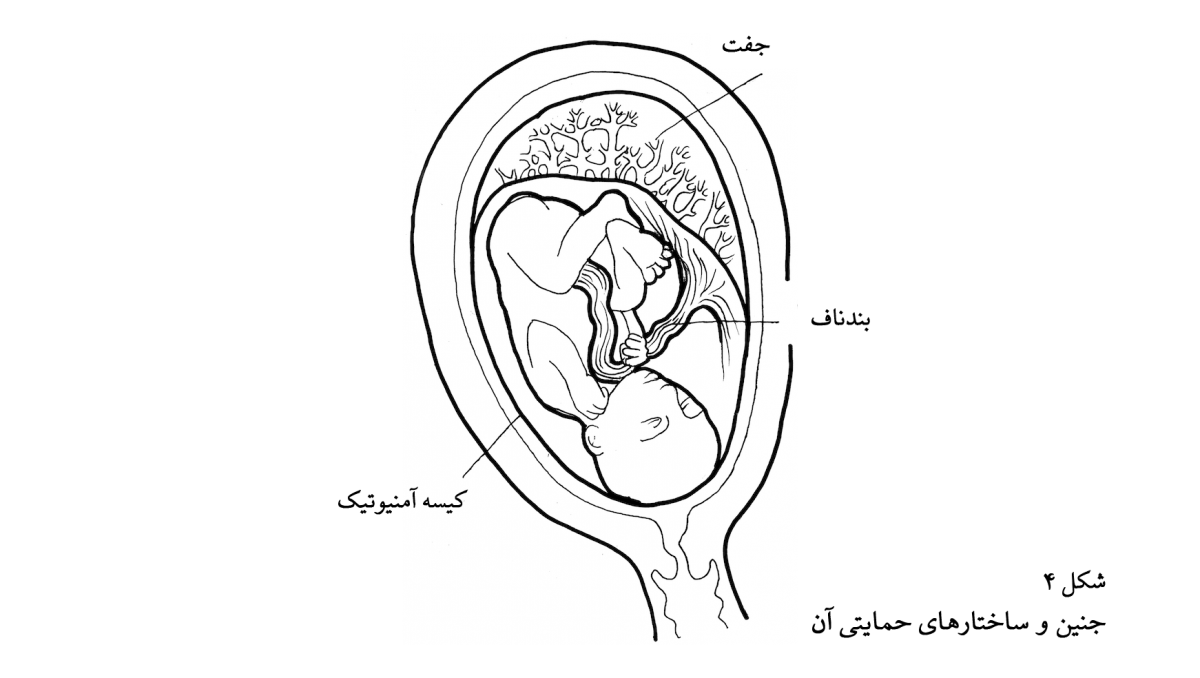

حال، با در نظر گرفتن این اطلاعات، آیا میتوان گفت که یکپارچگیِ بلاستوسیت آن اندازه هست که آن را یک موجود زنده در نظر بگیریم و بگوییم این نخستین تجسمِ لری است؟ بیشک، بلاستوسیست وحدتی بیش از کیسهی تیلهها دارد، اما تمام ویژگیهای یک موجود زنده را ندارد: هنوز رشد نمیکند (به علت وجود پردهی شفاف تخمک)، و راهی برای حفظ ثبات خود ندارد. با این حال، حتی اگر مسئلهی وحدت را کنار بگذاریم، دلایلی دیگری وجود دارند که بلاستوسیست را سرآغاز لری ندانیم. بلاستوسیست حاوی تمام محتویات رویان و ساختارهای حمایتیِ آن است. در واقع، ۸۵ درصد بلاستوسیست به ساختارهای حمایتی و ۱۵ درصد آن به جنین تبدیل خواهد شد. بلاستوسیست در روز چهارم مجموعهای از جنین و ساختارهای حمایتی آن است (شکل ۴) و صرفاً تداومِ جنین نیست. اگر بتوان منشأ لری، پسر پنج سالهی شما را صرفاً در جنین بالغ نه ماهه، هشت ماهه، شش ماهه، و .... جست، و منشأ این جنین بالغ در کلیت بلاستوسیست نباشد، در این صورت کلیت بلاستوسیست منشأ لری نیست.

آیا نمیتوان گفت که بخشی از بلاستوسیست (یعنی تودههای یاختهایِ بلاستوسیست) منشأ رویانِ بالغ است؟ نه، و علت آن جغرافیای این تودهها است. بخشی از این توده به جنین و بخشی به ساختارهای حمایتی آن تبدیل میشوند، و در نتیجه آنچه در روز چهارم وجود ندارد تمایز کامل میان یاختهها است. تمایزی نسبی وجود دارد، اما این تمایز کامل نیست. با وجود این تمایز نسبی، جنین در حالت ابتدایی و ساختارهای حمایتی در حالت ابتدایی هنوز تا اندازهای در هم آمیختهاند و نمیتوان چیزی را به عنوان نخستین تجسمِ جنین مشخص کرد؛ و در نتیجه، چیزی که بتواند لری خوانده شود وجود ندارد. به این ترتیب، برای آن که روز چهارم را سرآغاز لری بدانیم بسیار زود است؛ تا روز چهاردهم، وضع به همین قرار است. در تمام این روزها، تمایزی بین جنین و ساختارهای حمایتی وجود ندارد.

در این استدلال، منشأ لری صرفاً جنین بالغ است و نه جنین به علاوهی ساختارهای حمایتی. هرچند این استدلال در ابتدا موجه به نظر میرسد، ممکن است شما برای دفاع از دیدگاهی که سرآغاز لری را بلاستوسیست در روز چهارم، یا روز پنجم (بیرون آمدن از پردهی شفاف)، یا روز ششم (قرار گرفتن در دیوارهی رحم) میداند، بگویید که منشأ لری جنین بالغ و ساختارهای حمایتی آن است. ممکن است بگویید لری این اجزای خارجی را در هنگام زایمان از دست میدهد، درست همانطور که در آینده ناخن، مو، و یاختههای پوستی از دست خواهد داد. این دیدگاه ممکن است با فهم عمومی همخوانی نداشته باشد اما نامربوط نیست.

حدود چهارده روز پس از لقاح، زمانی که شیار اولیه (نخستین نشانههای ستون فقرات) پدید میآید، تمایز کامل به وقوع پیوسته است: بخشی مجزایی از رویان به جنین و سایر بخشها به ساختارهای حمایتی تبدیل شدهاند. این بخش جنینی از رویانِ چهارده روزه منشأ جنین بالغ، به عنوانی امری مجزا از ساختارهای حمایتی، است. اگر شما لری، به عنوان یک جنین بالغ صرف، را در نظر بگیرید و باور داشته باشید که ساختارهای حمایتی هرگز جزئی از او نیستند، منشأ او را میتوانید در روز چهاردهم بیابید و نه زودتر از آن. پیش از آن روز، رویان ترکیبی از ساختارهای حمایتی و جنین است و در نتیجه هیچ جزئی از آن را نمیتوان به عنوان شکل ابتداییِ لری مشخص و تعیین کرد.